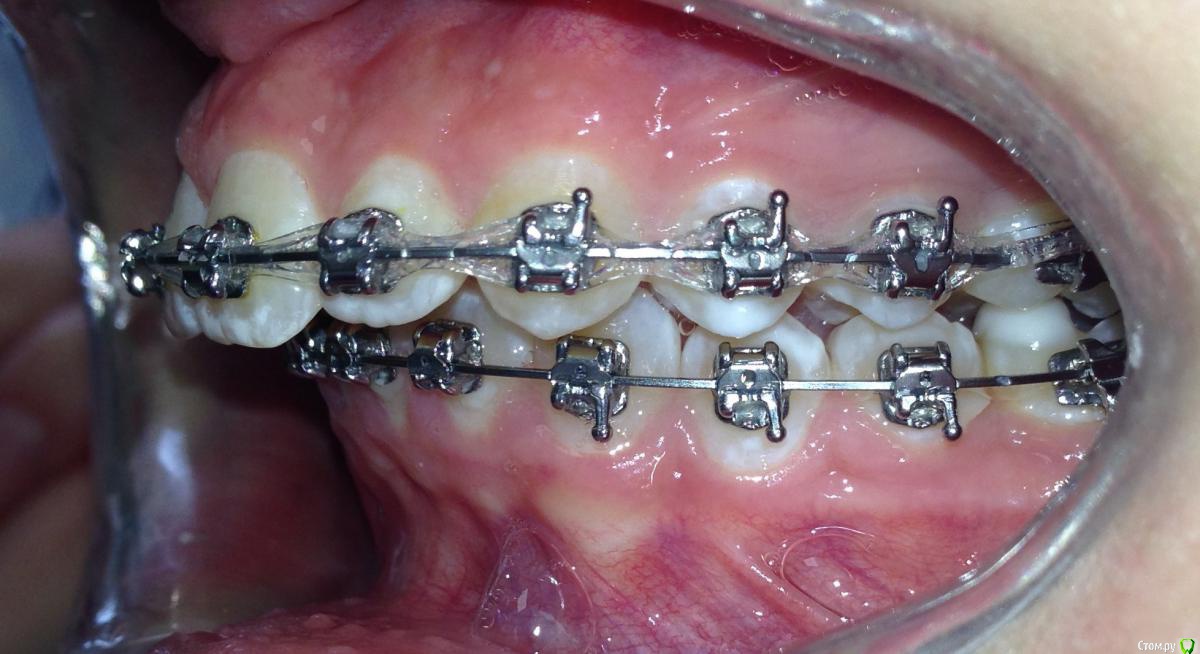

post-38874-0-87186300-1459536185_thumb.jpgpost-38874-0-15339500-1459536188_thumb.jpgpost-38874-0-82577500-1459536190_thumb.jpgpost-38874-0-61079300-1459536193_thumb.jpgpost-38874-0-22178300-1459536196_thumb.jpgpost-38874-0-56404400-1459536198_thumb.jpgpost-38874-0-43380300-1459536199_thumb.jpgpost-38874-0-04081600-1459536228_thumb.jpgpost-38874-0-34503200-1459536230_thumb.jpgpost-38874-0-34236500-1459536233_thumb.jpgpost-38874-0-95387400-1459536234_thumb.jpgpost-38874-0-86290600-1459536242_thumb.jpgpost-38874-0-47956700-1459536252_thumb.jpgpost-38874-0-98507600-1459536273_thumb.jpgpost-38874-0-52220700-1459536283_thumb.jpgpost-38874-0-12327700-1459536263_thumb.jpg

Извините за качество фото.

Пациентка 14 лет. Было принято решение лечить без удаления, тк. профиль не позволяет да и ретропозиция нч. Лечение идет. Я назначила ранние эластики слабые, на 17/25 нити на вч и 18 нити на нч. по 2 классу короткие 3,4-4,5. Пациентка пришла через месяц жалуется на щелканье челюсти во время ношения эластиков и сразу после их снятия. Т.е. если открывает рот, то челюсть скачкообразно двигается и щелчками. Последние 2 недели, когда много говорит, то вообще стала заедать. Это она так сказала. После отмены эластиков (страшно), через неделю пришла, рот открывает ровно, без девиации, щелчков нет. Вопрос: почему щелкает и что с этим делать? По поводу прикуса, посоветуйте, пожалуйста, как нормализовать? Аппарат типа гербста? может ей твинблок сделать? Эластики? К сожалению другими методами я пока что не владею. Спасибо, очень жду ваших советов.